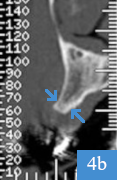

coupe panoramique de dentascanner, 4 mois après la greffe osseusecoupe coronale de dentascanner, hauteur osseuse de 12 mm

Dentascanner 4 mois après la greffe

2a : greffon osseux visible, positionné à l'endroit où il manquait de la hauteur d'os

2b : os sous le sinus mesuré à 12 mm de hauteur ; pose d'un implant possible